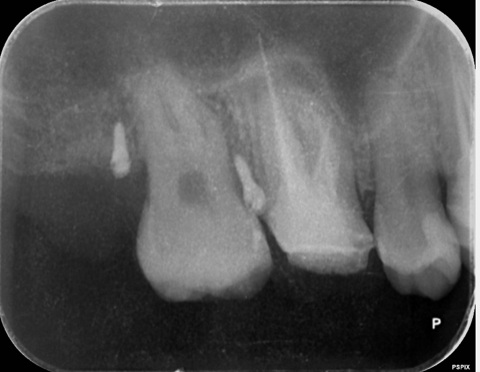

【グランドメゾンデンタルクリニック】抜歯後の骨...